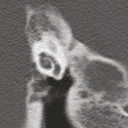

Deep learning based medical image segmentation models usually require large datasets with high-quality dense segmentations to train, which are very time-consuming and expensive to prepare. One way to tackle this challenge is by using the mixed-supervised learning framework, in which only a part of data is densely annotated with segmentation label and the rest is weakly labeled with bounding boxes. The model is trained jointly in a multi-task learning setting. In this paper, we propose Mixed-Supervised Dual-Network (MSDN), a novel architecture which consists of two separate networks for the detection and segmentation tasks respectively, and a series of connection modules between the layers of the two networks. These connection modules are used to transfer useful information from the auxiliary detection task to help the segmentation task. We propose to use a recent technique called "Squeeze and Excitation" in the connection module to boost the transfer. We conduct experiments on two medical image segmentation datasets. The proposed MSDN model outperforms multiple baselines.